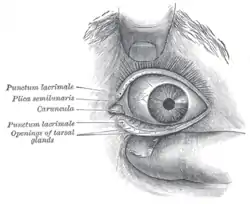

Front of left eye with eyelids separated to show medial canthus and openings of meibomian (tarsal) glands | |